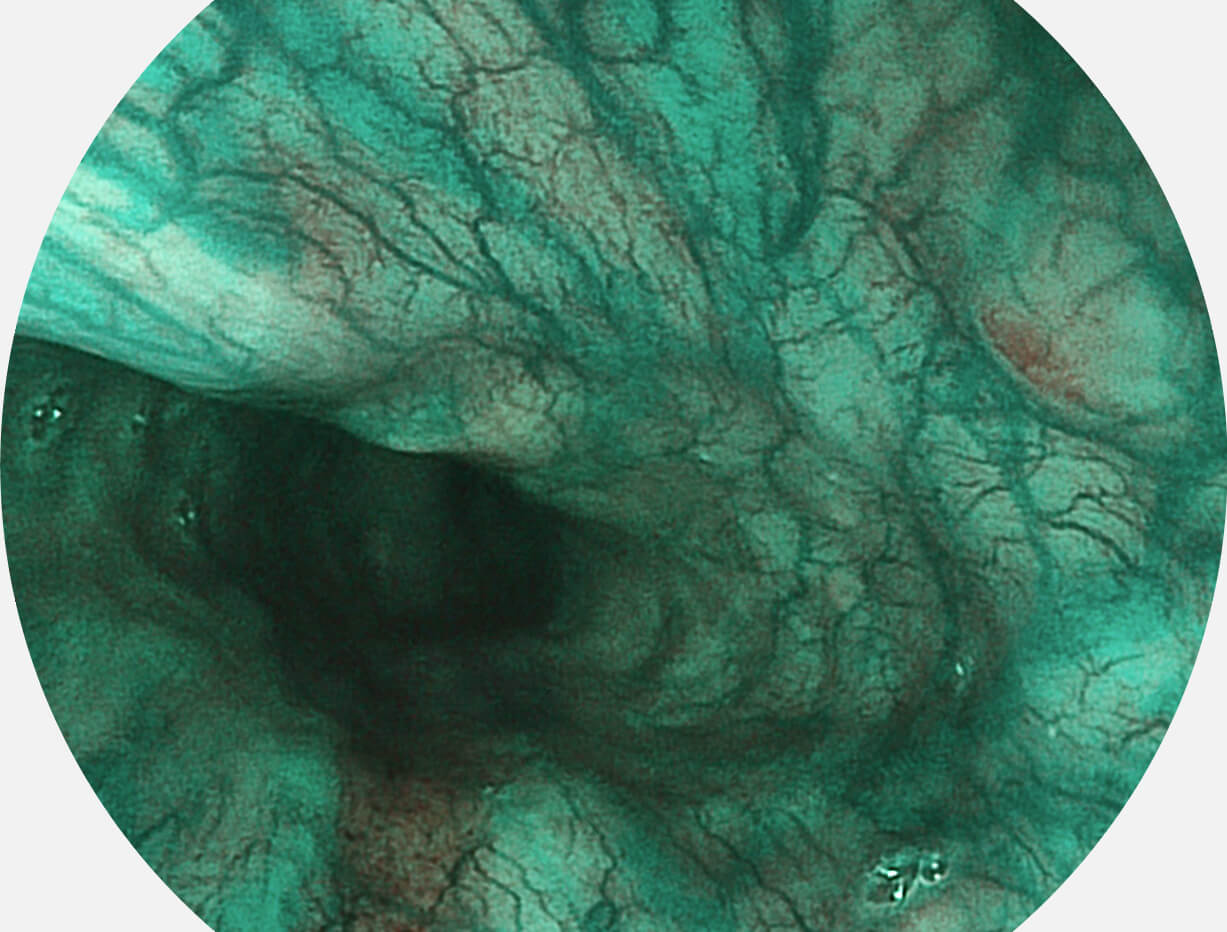

Spectral Focused lmaging, SFI

图像具有高亮度、高黏膜血管颜色对比度的特点,且不改变粘液、食物残渣、粪便的基本颜色,可在中远景下进行观察,助力消化道早期疾病的诊断。

SFI图像

白光图像

采用光路合束技术,光谱自由度高,实现了更丰富的照明模式,染色模式SFI及VIST,从远景到近景,助力消化道早期疾病诊断。